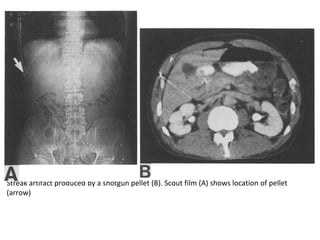

STREAK ARTIFACT

• One of the basic assumptions in CT scanning is

that each detector, at every position, will

observe some transmitted radiation. If a high

density material severely reduces the

transmission, the detector may record no

transmission. This violates the basic

assumption, and the reconstruction program

will not account for such a violation.

Streak artifact produced by a shotgun pellet (B). Scout film (A) shows location of pellet

(arrow)